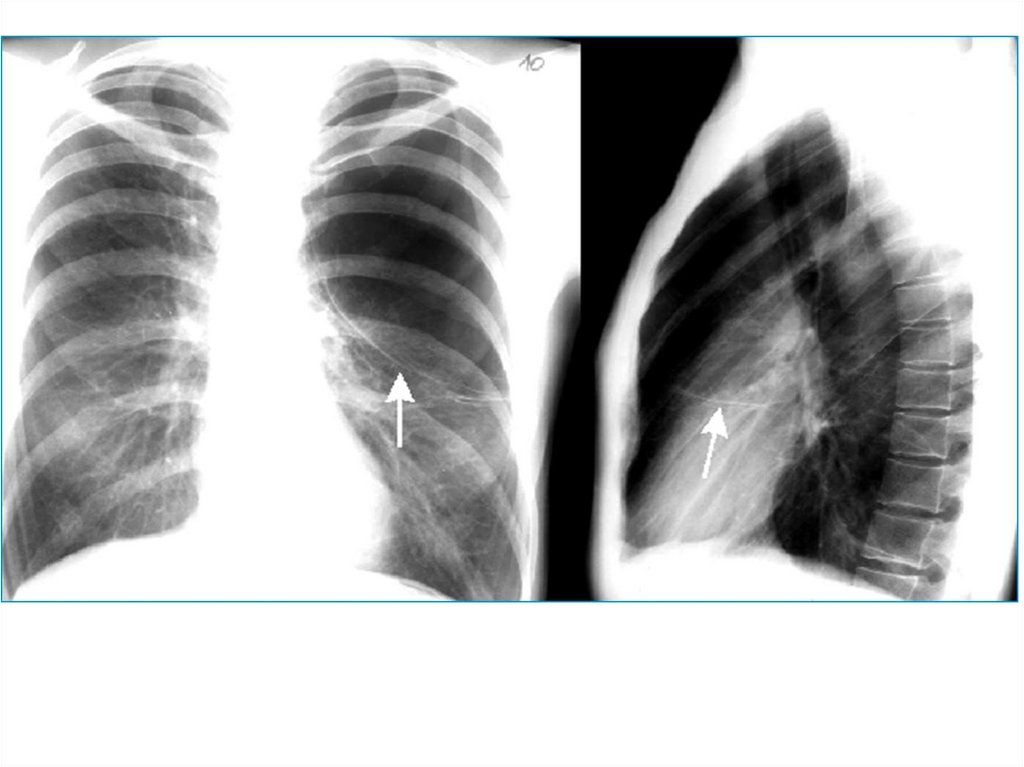

21. Обструкция бронха

Или обтурационная эмфизема, которая

развивается в результате бронхиальной астмы,

пневмонии, бронхита, бронхиолита,

пневмосклероза.

Видимая картина – тотальное одностороннее

просветление пораженного легкого.

23. Компенсаторная эмфизема

В случае ателектаза/удаления другого легкого.

Видимая картина – тотальное односторнее

просветление легкого, смещение средостения в

другую сторону.